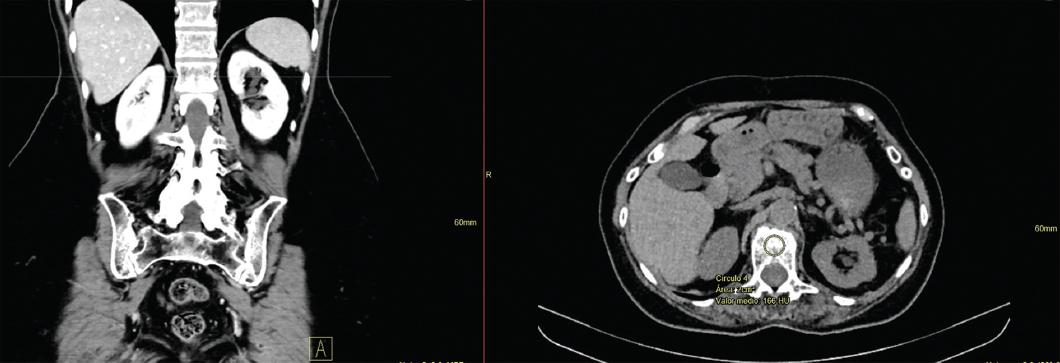

To determine HU, axial slice images with soft tissue windows at the L1 level were evaluated retrospectively using Enterprise imaging Xero viewer 8. 1. 4. 150. Soft tissue and bone windows were used to view the images. Coronal slices were used as a reference to locate L1. For measurement standardization, a 2 cm2 region of interest was determined within the trabecular bone in the L1 vertebral body, excluding the cortical margin. Then, the attenuation was measured through HU (Fig. 1).